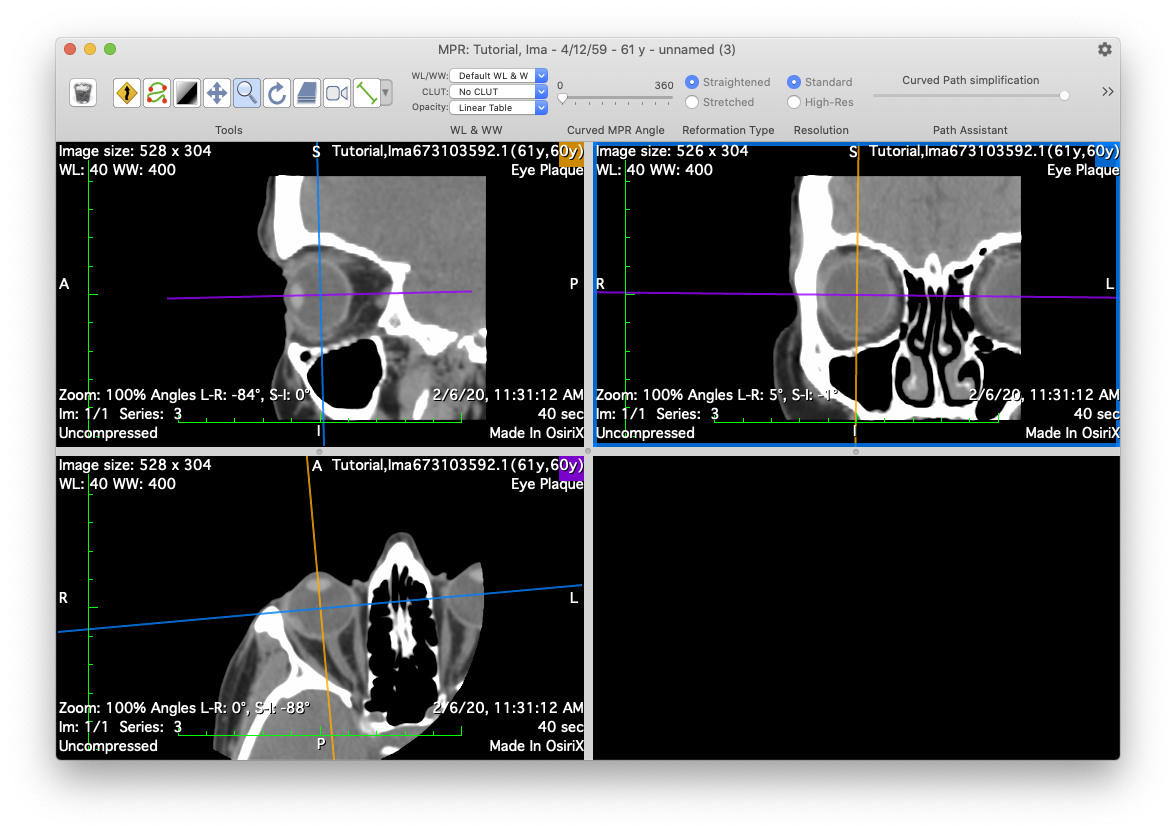

MPR

The orbital CT (or MRI) series is used to create these seven reconstructions that are used to build the 3D model of the eye. That 3D model is used to calibrate the fundus image, measure the optic nerve sheath diameter, and determine suture eyelet coordinates on the eye. If the tumor happens to be large enough to be visible in these reconstructions, the CT also provides confirmation of tumor location, shape and elevation as determined from the fundus and ultrasound imaging.

axial

Axial bisecting reconstruction. Used to determine optic disc center, nerve sheath diameter, and anterior oblateness of the eye. The sheath diameter determines how closely the plaque shell and seeds can approach the disc. This distance becomes important for extremely posterior and peripapillary tumors.

equator

Coronal bisecting reconstruction at the equator. Used to verify cylindrical symmetry

sagittal

Sagittal bisecting reconstruction. Used to verify cylindrical symmetry and anterior oblateness

nerve

Coronal plane through the posterior sclera and optic nerve. This reconstruction helps to approximate the center of the optic disc and the diameter of the sheath surrounding the optic nerve. The sheath diameter determines how closely the plaque shell and seeds can approach the disc. This distance becomes important for extremely posterior and peripapillary tumors.

n-axial

Axial bisector illustrating the nerve-coronal plane (blue axis)